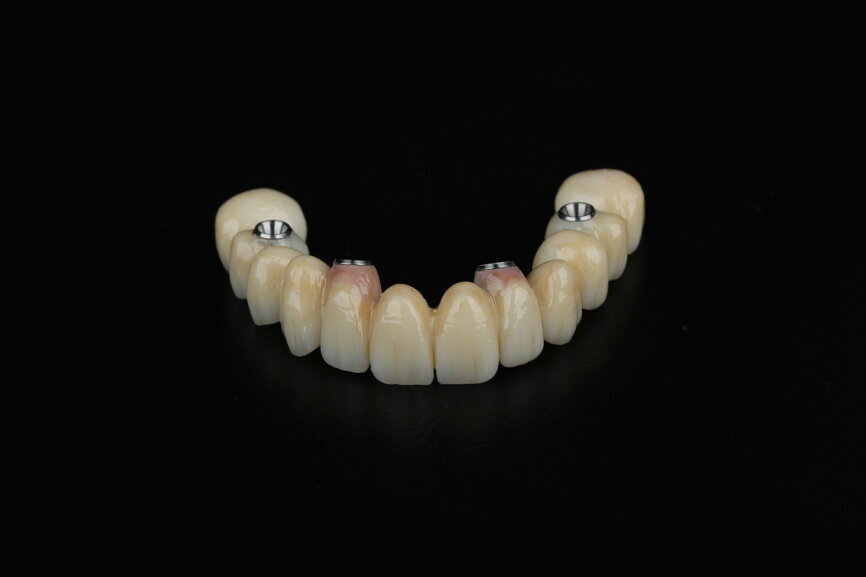

To design the prosthesis digitally, we first selected the screw-retained abutment (SRA) angle and gingival height (Fig. 14) and then we created the patient model on which we could connect the BLX implants with the SRAs selected from the Straumann library (Fig. 15). The implant placement guide was on the model, leveraging the high stability that we could gain from palatal support (Figs. 16 & 17). After printing the model, the BL  implant analogues were positioned using the template for navigation. The digital planning using coDiagnostiX (Version 9.14) allowed the dental technician to identify all the necessary parameters related to implant position (Figs. 18–22). Emergence profiles were set-up on the model (Fig. 23). The model was scanned using scan bodies, and a CAD/CAM temporary restoration was designed and milled in a PMMA-based restorative material (Figs. 24–29).

At this time, we were able to make a few modifications to the zirconia frame. The design of the zirconia temporary restoration was sent to the milling unit and produced on a full-contour zirconia disc. The zirconia frame was then cemented on Variobase copings (Straumann) as an interface to be screwed on to the SRAs (Figs. 63 & 64).